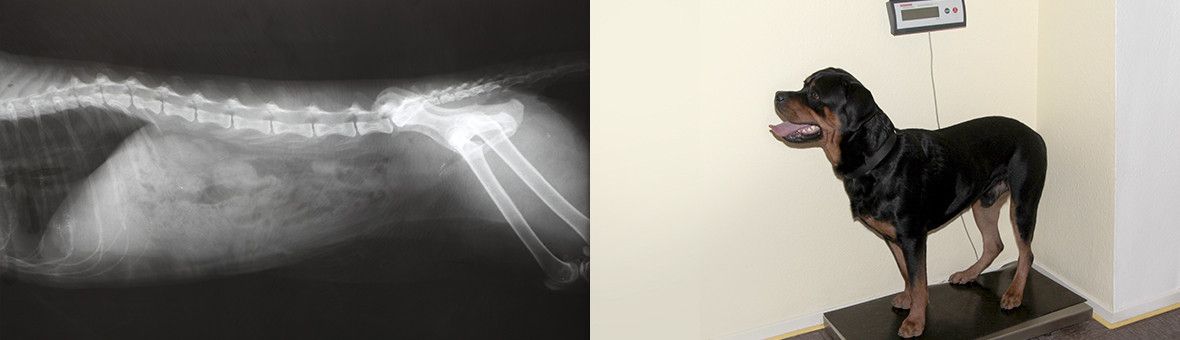

- Röntgenuntersuchungen